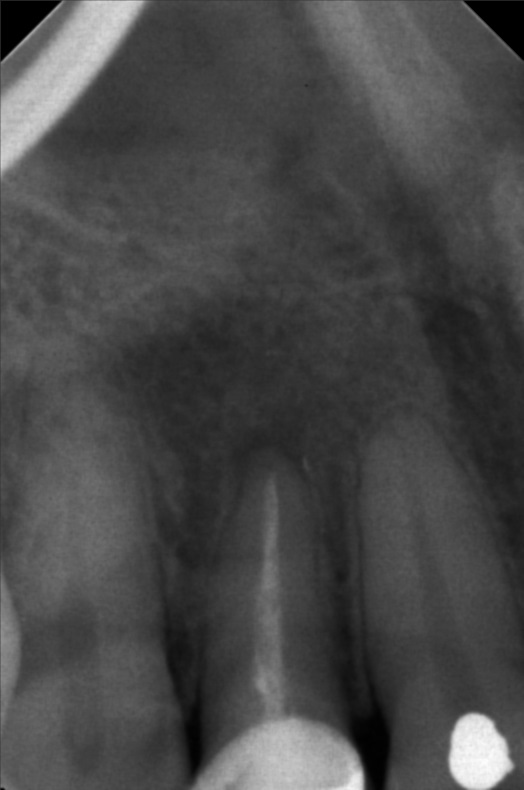

- 9/24/22 - Check up & Xray 10/01/22 - RCT 18mm , formacresol #35 10/08/22- RCT 17mm, campenol 10/15/22- 17.5MM PULP DEVITALIZER PAD done 11/05/22- Zirconia/LC 16 11/19/22- OP/Install Of Crowns